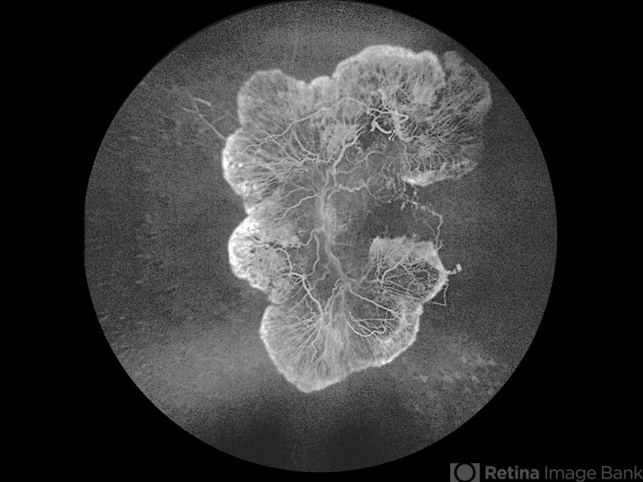

- proliferative diabetic retinopathy (PDR), Neovascularisation at the Disc (NVD)

- Fluorescein angiogram of a monocular young diabetic with florid NVD.